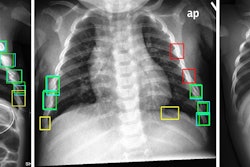

Neuromorphic AI leverages the firm's hyperdimensional computing and deep-learning technologies to assist radiologists and healthcare providers in diagnosing multiple chest conditions from x-ray images. Key features include an advanced spatial transformer network designed to improve the precision of image analysis and hyperdimensional computing encoding for pattern recognition and multi-label classification, according to the company.